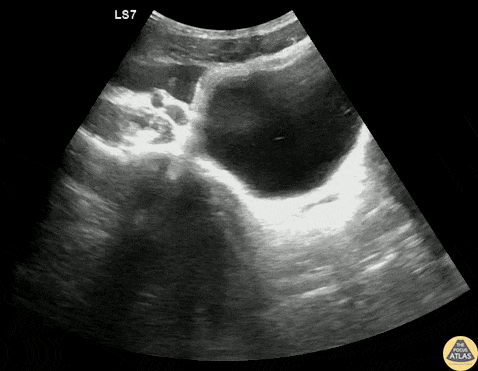

Trauma - Pelvic +FAST from Splenic Injury

A teenage male patient presented to the ED after a helmeted mountain bike crash, and due to mechanism, underwent a bedside FAST exam, which was positive in the RUQ as well as suprapubic views. CT demonstrated a grade 4 spleen laceration as well as multiple buckle rib fractures, and he was admitted for observation. Dr. Gabe Siegel, PGY-2 and Dr. Michael Kidon, PGY-4 Denver Health Residency in Emergency Medicine